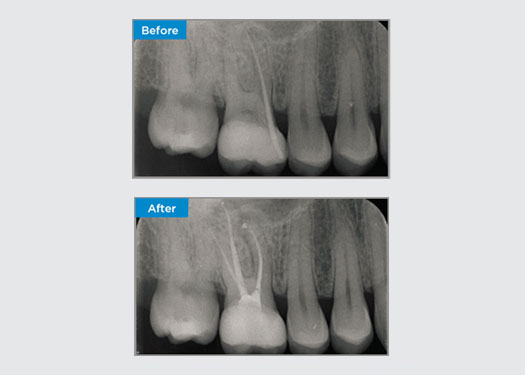

The patient presented with asymptomatic apical periodontitis on tooth 34. From the pre-op radiograph, tooth 34 was noted with two visible roots. However, a CBCT scan confirmed a three rooted premolar, and the canals divided into three at the mid root. A careful file selection is critical for this delicate tooth.

Dr Jack Lin, Endodontist, Sydney, NSW Australia

In this situation, tooth/root structure preservation is essential to reduce the risk of ledging, transportation, zipping, perforation, and root fracture. Case selection, diagnosis, and pre-treatment planning are important. Endodontic file selection with flexibility, efficiency, and respect of natural root anatomy is critical.